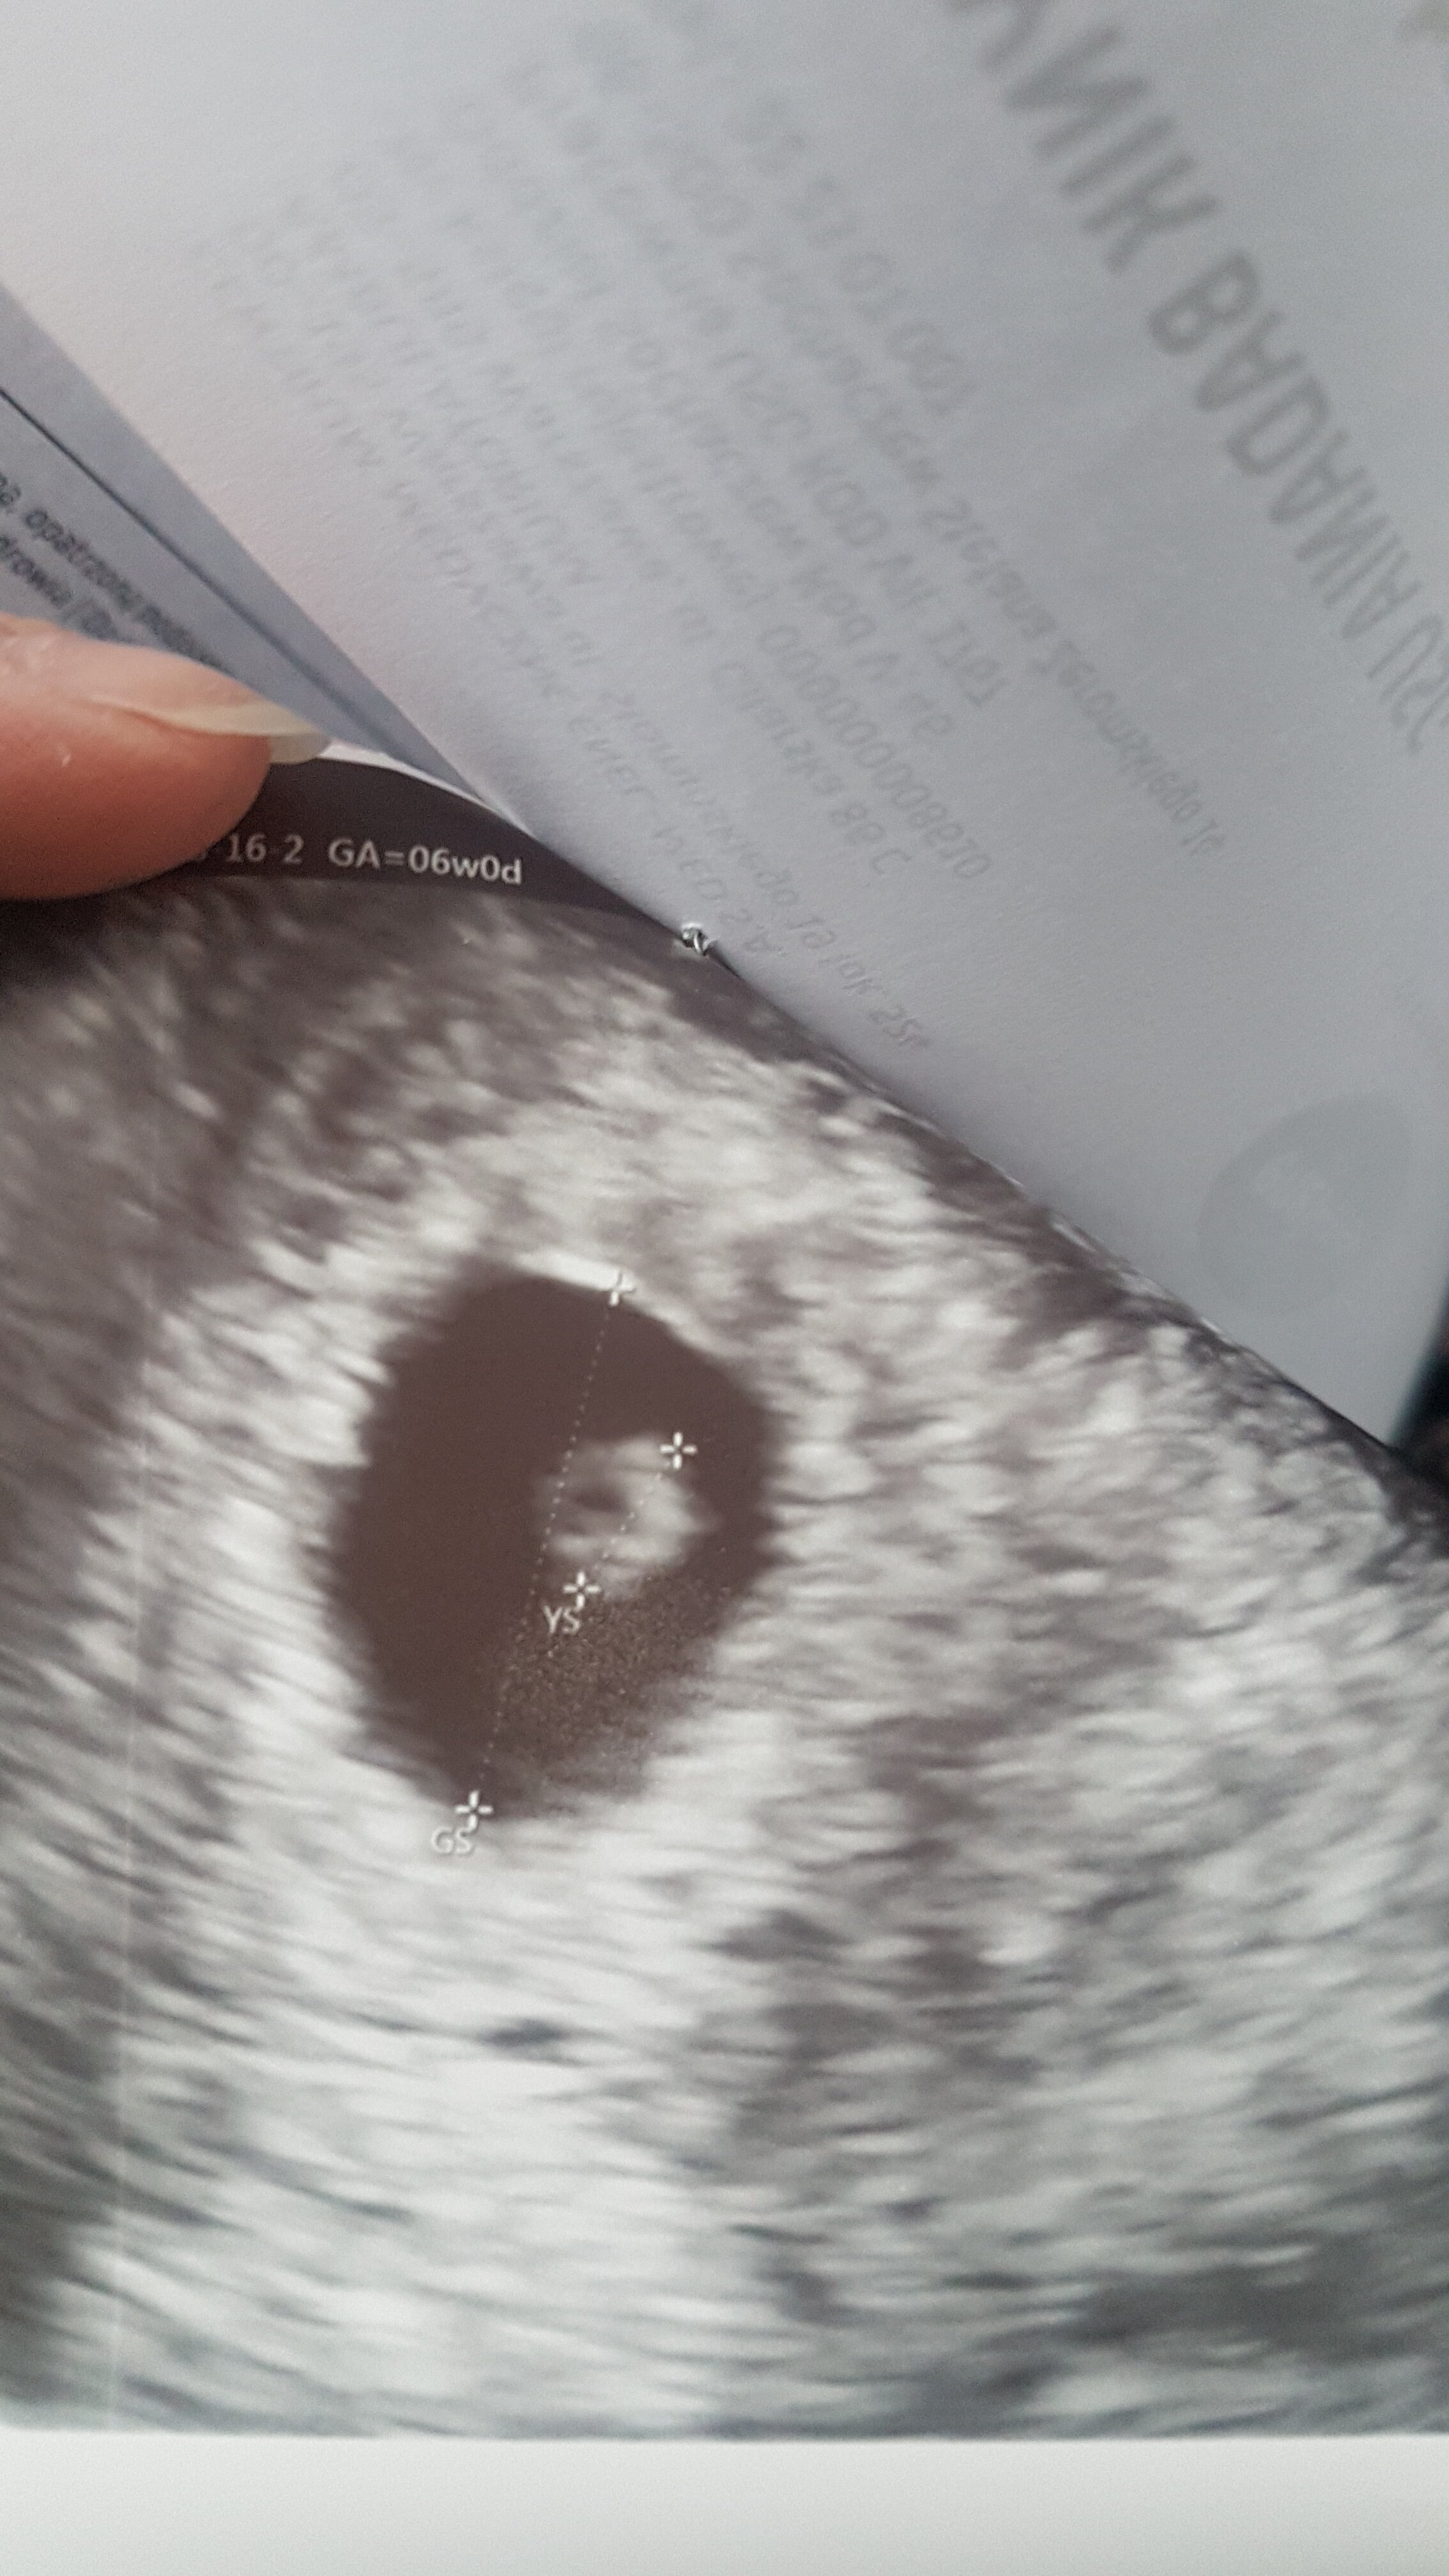

Po wizycie i zarodka brak. Jest pęcherzyk ciążowy (ale za mały na tydzień z OM) i pęcherzyk żółtkowy, ale zarodka nie widać. Mam jutro powtórzyć betę, jeśli ciąża się rozwija to powina być koło 15-17 tysięcy i wtedy za tydzień kolejne USG.

Podłamałam się, jakoś nie dopuszczałam do siebie myśli, że znów może być coś źle, a tu duża szansa na puste jajo.

Na USG mam napisane 6+0

Doktor powiedział, że zarodka poniżej 2 mm aparat nie wyłapie. Powiedział że albo jest jeszcze za mały albo już go nie ma.